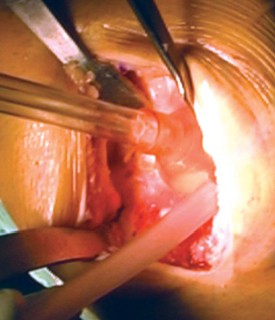

الخطوة 3: قطع عظم الساق (Tibial Cut)

- الدليل خارج النخاع (Extramedullary Guide): يُستخدم دليل خارج النخاع لقطع عظم الساق.

- إزالة الرباط الصليبي الأمامي (ACL): يتم قطع الرباط الصليبي الأمامي من موضع ارتباطه.

- تحريك الساق للأمام: تُحرك الساق للأمام (subluxed) لزيادة كشف الجزء العلوي من عظم الساق.

- وضع الدليل: يُوضع الدليل خارج النخاع فوق الثلث الإنسي من الحدبة الظنبوبية، بمحاذاة عرف الساق، وفي مركز مفصل الكاحل.

- تحديد الميل: يُحدد الميل المناسب ويُثبت الدليل في مكانه.

- القطع والحماية: تُحمى الأربطة الجانبية بالمبعدات، ويُقطع عظم الساق بشكل عمودي على محوره.

-

اعتبارات هامة (Pitfalls):

- يجب تجنب القطع المائل لعظم الساق (varus cut) بأي ثمن. يرتبط القطع المائل لعظم الساق في أي عملية استبدال مفصل الركبة بزيادة معدلات الفشل، خاصة في المرضى الذين يعانون من السمنة المفرطة. يحرص الأستاذ الدكتور محمد هطيف على الدقة القصوى لتجنب هذا الخطر.